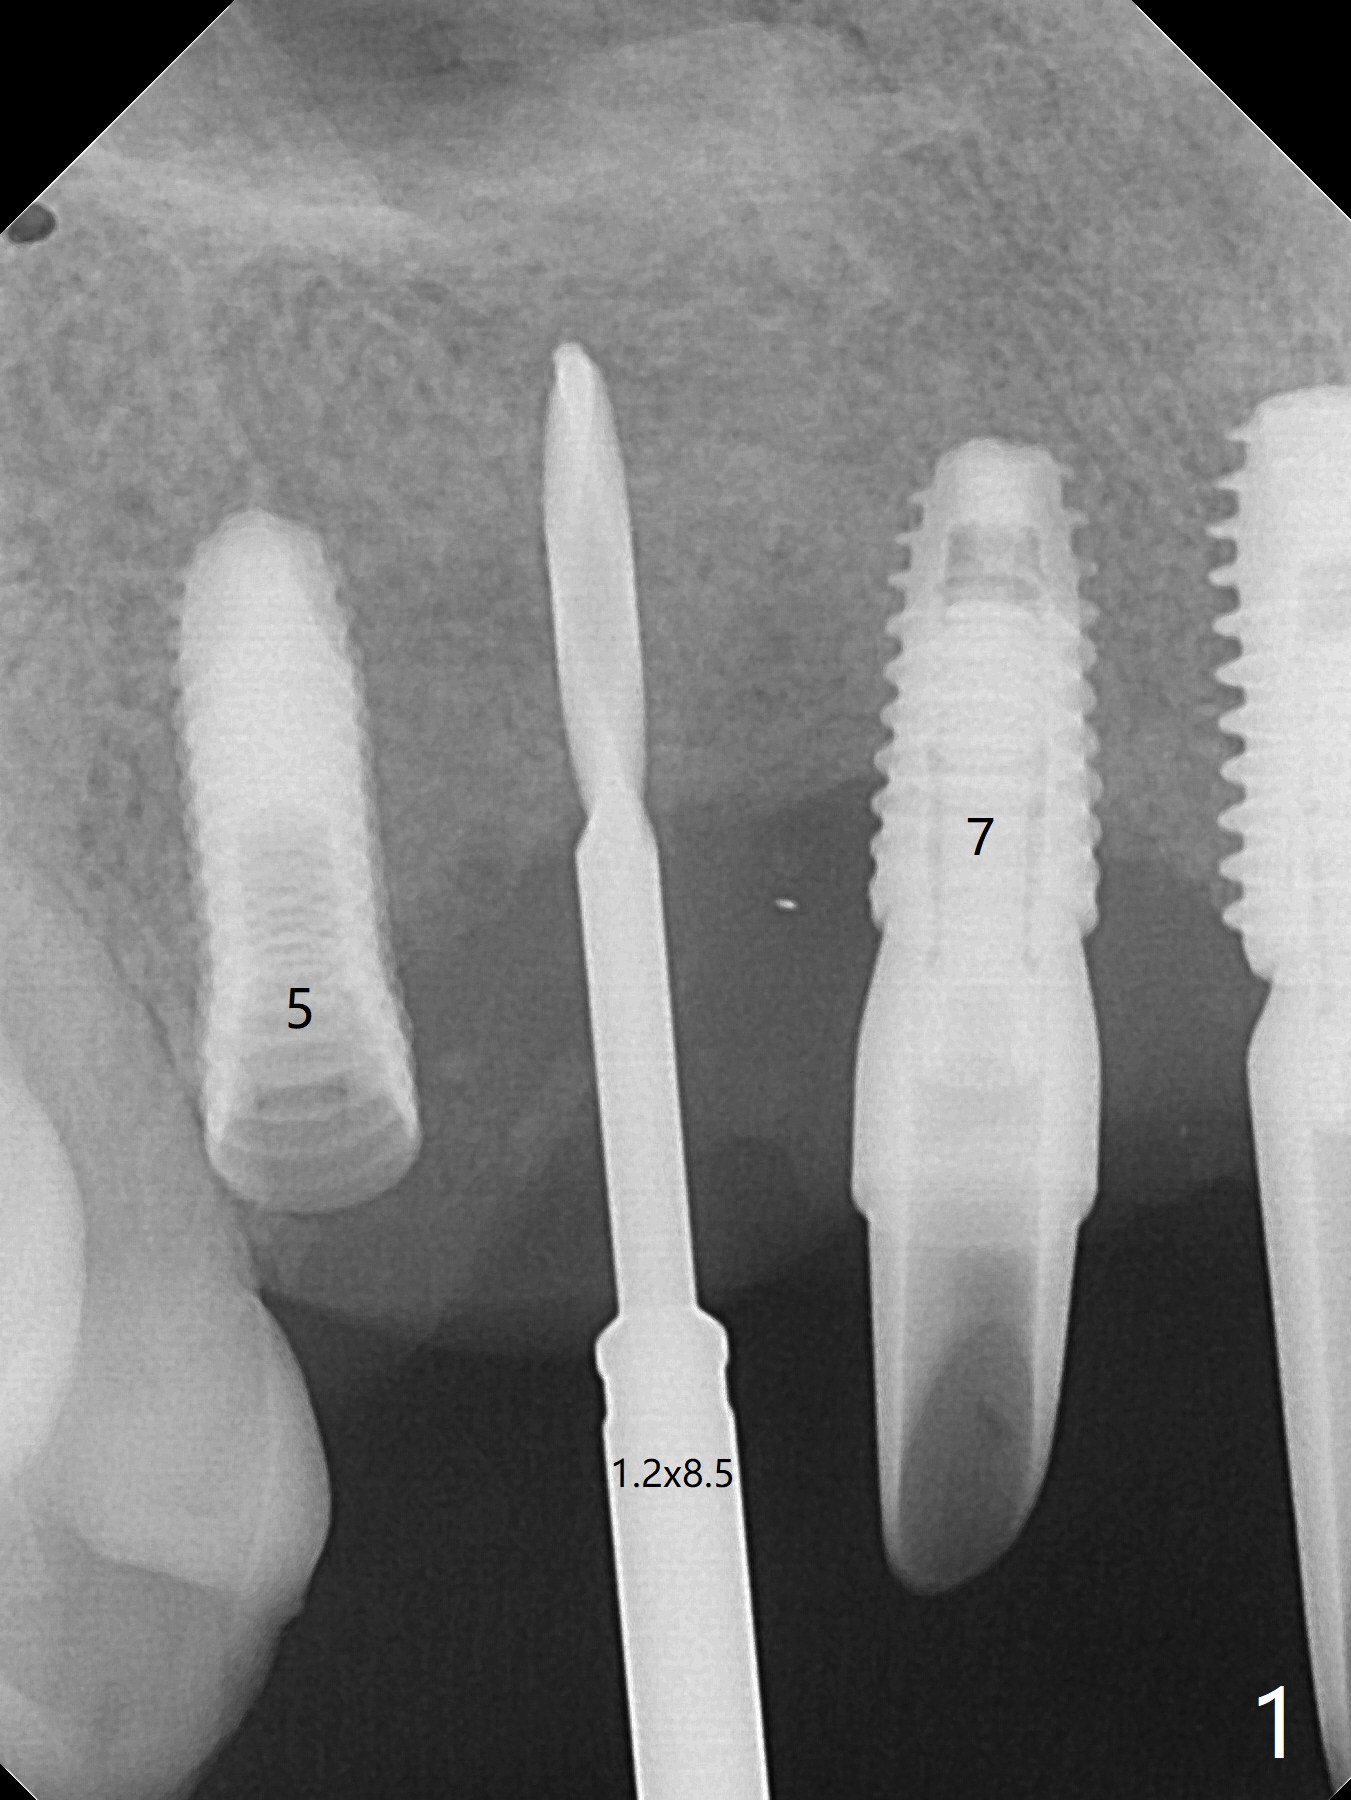

5,7号牙两段式植体种植后螺纹暴露,植骨后4-5个月,准备5号牙uncover,病人主诉7号牙出血,切开后发现两个植体螺纹仍旧暴露(图一,二),看样子保留不住,而6号牙位牙槽嵴不宽,准备植入2x8.5毫米一段式植体,结果骨质高度允许植入10毫米植体(图二,三),然后使用外科钻头和环形刀(trephine bur)取出两段式植体,填入粘性骨粉(图三:*),覆盖PRF和不可吸收膜,4-0 PGA缝合(图四),最后牙周敷料。5,7牙位愈合也可以植入一段式植体,让植体之间距离大些,植骨后颊侧腭侧宽度也可能不足。